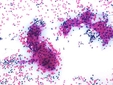

4. BiyopsiLenfoma tanısının kesinleştirilmesi için en kritik test biyopsidir. Biyopsi türleri şunlardır:

Biyopsi sonuçları, lenfoma türünü ve evresini belirlemede kritik öneme sahiptir. 5. Moleküler TestlerBiyopsi yapılan dokulardan elde edilen örneklerde, lenfomanın genetik ve moleküler özelliklerini değerlendiren testler yapılabilir. Bu testler, tedavi seçeneklerinin belirlenmesine yardımcı olur. Ek BilgilerLenfoma tanısı koymak, multidisipliner bir yaklaşım gerektirir. Hem hematologlar hem de onkologlar, hastanın durumunu değerlendirmek ve en uygun tedavi yöntemini belirlemek için birlikte çalışır. Ayrıca, lenfoma tedavisi genellikle kemoterapi, radyoterapi veya hedefe yönelik tedavi yöntemlerini içermektedir. Erken teşhis ve doğru tanı, hastalığın prognozunu önemli ölçüde etkileyebilir. Sonuç olarak, lenfoma tanısı koymak için bir dizi test ve değerlendirme süreci gereklidir. Hekimlerin bu testleri dikkatlice değerlendirmesi ve hastaların bireysel durumlarına uygun bir tedavi planı oluşturması, başarılı bir tedavi süreci için kritik öneme sahiptir. |